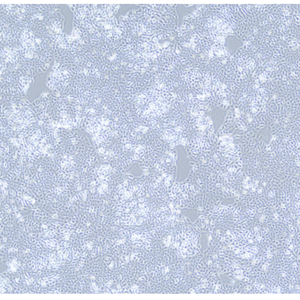

产品信息: